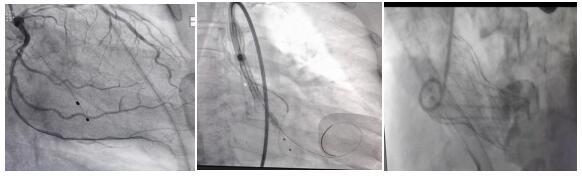

術(shù)前手術(shù)團(tuán)隊(duì)充分評(píng)估了手術(shù)中可能遇到的難點(diǎn)和風(fēng)險(xiǎn),制定了一套周密詳細(xì)的手術(shù)實(shí)施方案,并進(jìn)行了相應(yīng)的風(fēng)險(xiǎn)預(yù)案準(zhǔn)備(置臨時(shí)心臟起搏器、冠狀動(dòng)脈保護(hù)、濕備體外循環(huán)等)。3月11日,患者在全身麻醉的情況下先行左冠狀動(dòng)脈旋支支架置入手術(shù),隨后穿刺右側(cè)頸內(nèi)靜脈,送入臨時(shí)起搏電極至右心室尖部備用;在兩側(cè)腹股溝各切一個(gè)1cm多的小切口,左側(cè)作為輔助入路行股動(dòng)脈、股靜脈穿刺置管備體外循環(huán)使用。右側(cè)股動(dòng)脈作主入路,按照入路穿刺置動(dòng)脈鞘→導(dǎo)絲跨瓣→球囊擴(kuò)張→定位釋放→即刻評(píng)估的流程,順利安全置入了心臟瓣膜,術(shù)后造影及超聲提示未見(jiàn)明顯瓣周漏及瓣膜返流,瓣膜位置理想,形態(tài)良好,血流動(dòng)力學(xué)即刻改善,術(shù)中未出現(xiàn)相關(guān)并發(fā)癥,手術(shù)圓滿成功。術(shù)后1周治愈出院,現(xiàn)已恢復(fù)正常生活。

PCI術(shù)后 預(yù)釋放 釋放